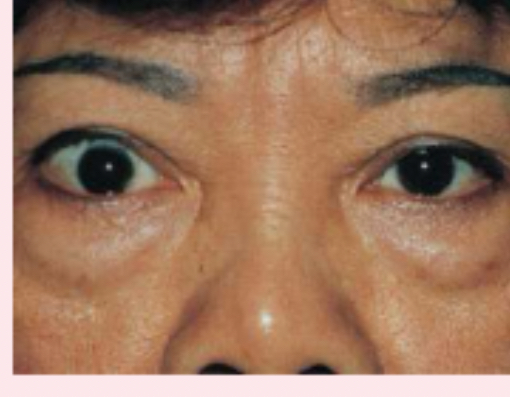

exophthalmos

protruding eyeballs and retracted eyelids